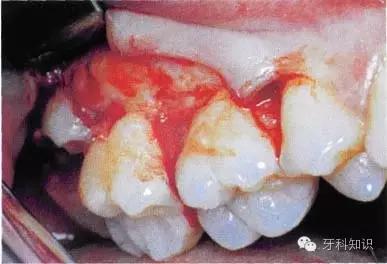

3.拔除患牙:将牙钳喙准确放置于患牙的唇舌侧或颊舌侧,使钳喙与牙齿长轴方向缓慢摇动,随着牙齿松动度增大,用力向外牵引拔出(图5-10,图5-11)。

单根牙牙根呈锥形者

,可以稍加旋转力量拔出。

单根牙牙根呈扁平状者(如

)和多根牙,应避免旋转力,并宜顺着牙根弯曲的方向拔出,否则易折断牙根。